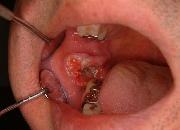

口腔がん

舌がん(舌のがん)